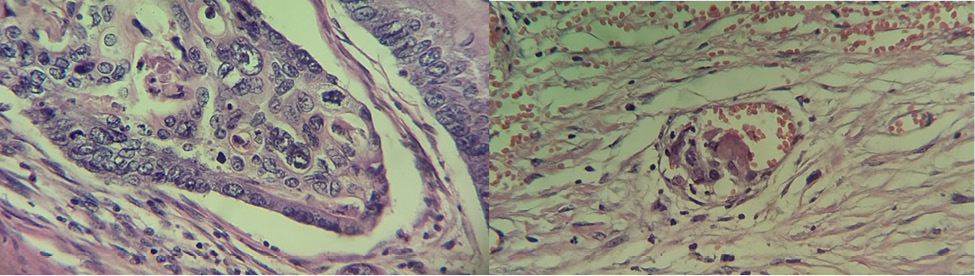

El departamento de Anatomopatología reporto la pieza como un adenocarcinoma de tipo intestinal moderadamente diferenciado con extensión hasta los tejidos blandos pericolónicos e invasión vascular (Figura 5 y 6).

Figura 5. Los cortes histológicos teñidos con tinción de rutina H&E muestran una proliferación difusa de elementos glandulares atípicos con anaplasia celular marcada y presencia de necrosis sucia intraluminal. Fuente: Laboratorio de Anatomopatología del HGZ No. 35.

Figura 6. Izquierda: el corte histológico muestra la anaplasia celular marcada y mitosis atípicas presentes. Derecha: se identifica invasión vascular por las células neoplásicas. Fuente: Laboratorio de Anatomopatología del HGZ No. 35.